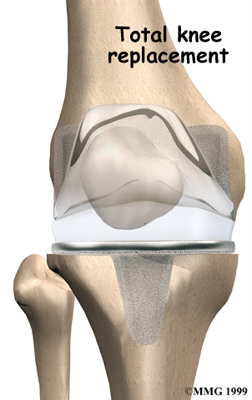

Artificial Knee Replacement

An artificial knee replacement is the ultimate solution for advanced knee OA.

Surgeons prefer not to put a new knee joint in patients younger than 60. This is because younger patients are generally more active and might put too much stress on the joint, causing it to loosen or even crack. A revision surgery to replace a damaged prosthesis is harder to do, has more possible complications, and is usually less successful than a first-time joint replacement surgery.

Related Document: FYZICAL Harker Heights Guide to Artificial Joint Replacement of the Knee